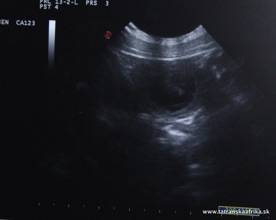

14.11. - 24. deň - sono - potvrdenie gravidity